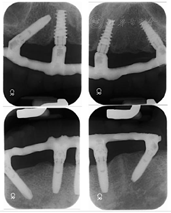

(4)下颌拔牙后4个月(2016年1月)复诊,口腔CBCT检查43、44区骨组织早期愈合(图7),牙槽嵴顶黏膜愈合良好(图8A),口腔局部阿替卡因肾上腺素注射液浸润麻醉,32、42区轴向植入Nobel Speedy4 mm×13 mm种植体,35区斜行植入Nobel Speedy4 mm×15 mm种植体,43、44区骨组织愈合不良,清理肉芽组织后呈凹坑型骨缺损(图8B),45区倾斜备洞穿越44、43骨缺损区植入Nobel Speedy4 mm×18 mm种植体(图8C),4颗种植体初期稳定性均达到35 N·cm,安装复合基台。43、44骨缺损区回填自体骨屑(图8D),修整牙龈、黏膜瓣复位,4-0可吸收缝线严密缝合创口。术后即刻制取印模,制作下颌种植固定过渡义齿并戴入,义齿修复到第二前磨牙,建立上下颌固定义齿咬合关系。(图9)。

种植修复后1、2、4年随访X线全颌曲面体层片显示种植体周围骨结合良好(图13A~C),患者对修复体美观及咀嚼功能效果满意。修复后6年(2022年8月)随访X线全颌曲面体层片及根尖片显示种植体周骨结合良好,上前牙区种植体颈部骨吸收约1 mm(图13D、图14)。取下上下颌义齿,清理义齿组织面滞留菌斑,清洁复合基台并检查基台中央螺丝稳定,清洁义齿组织面,戴回上下颌义齿(图15)。患者口腔卫生宣教,指导正确刷牙,使用冲牙器冲洗义齿与牙龈间缝隙,嘱6个月复查、维护。